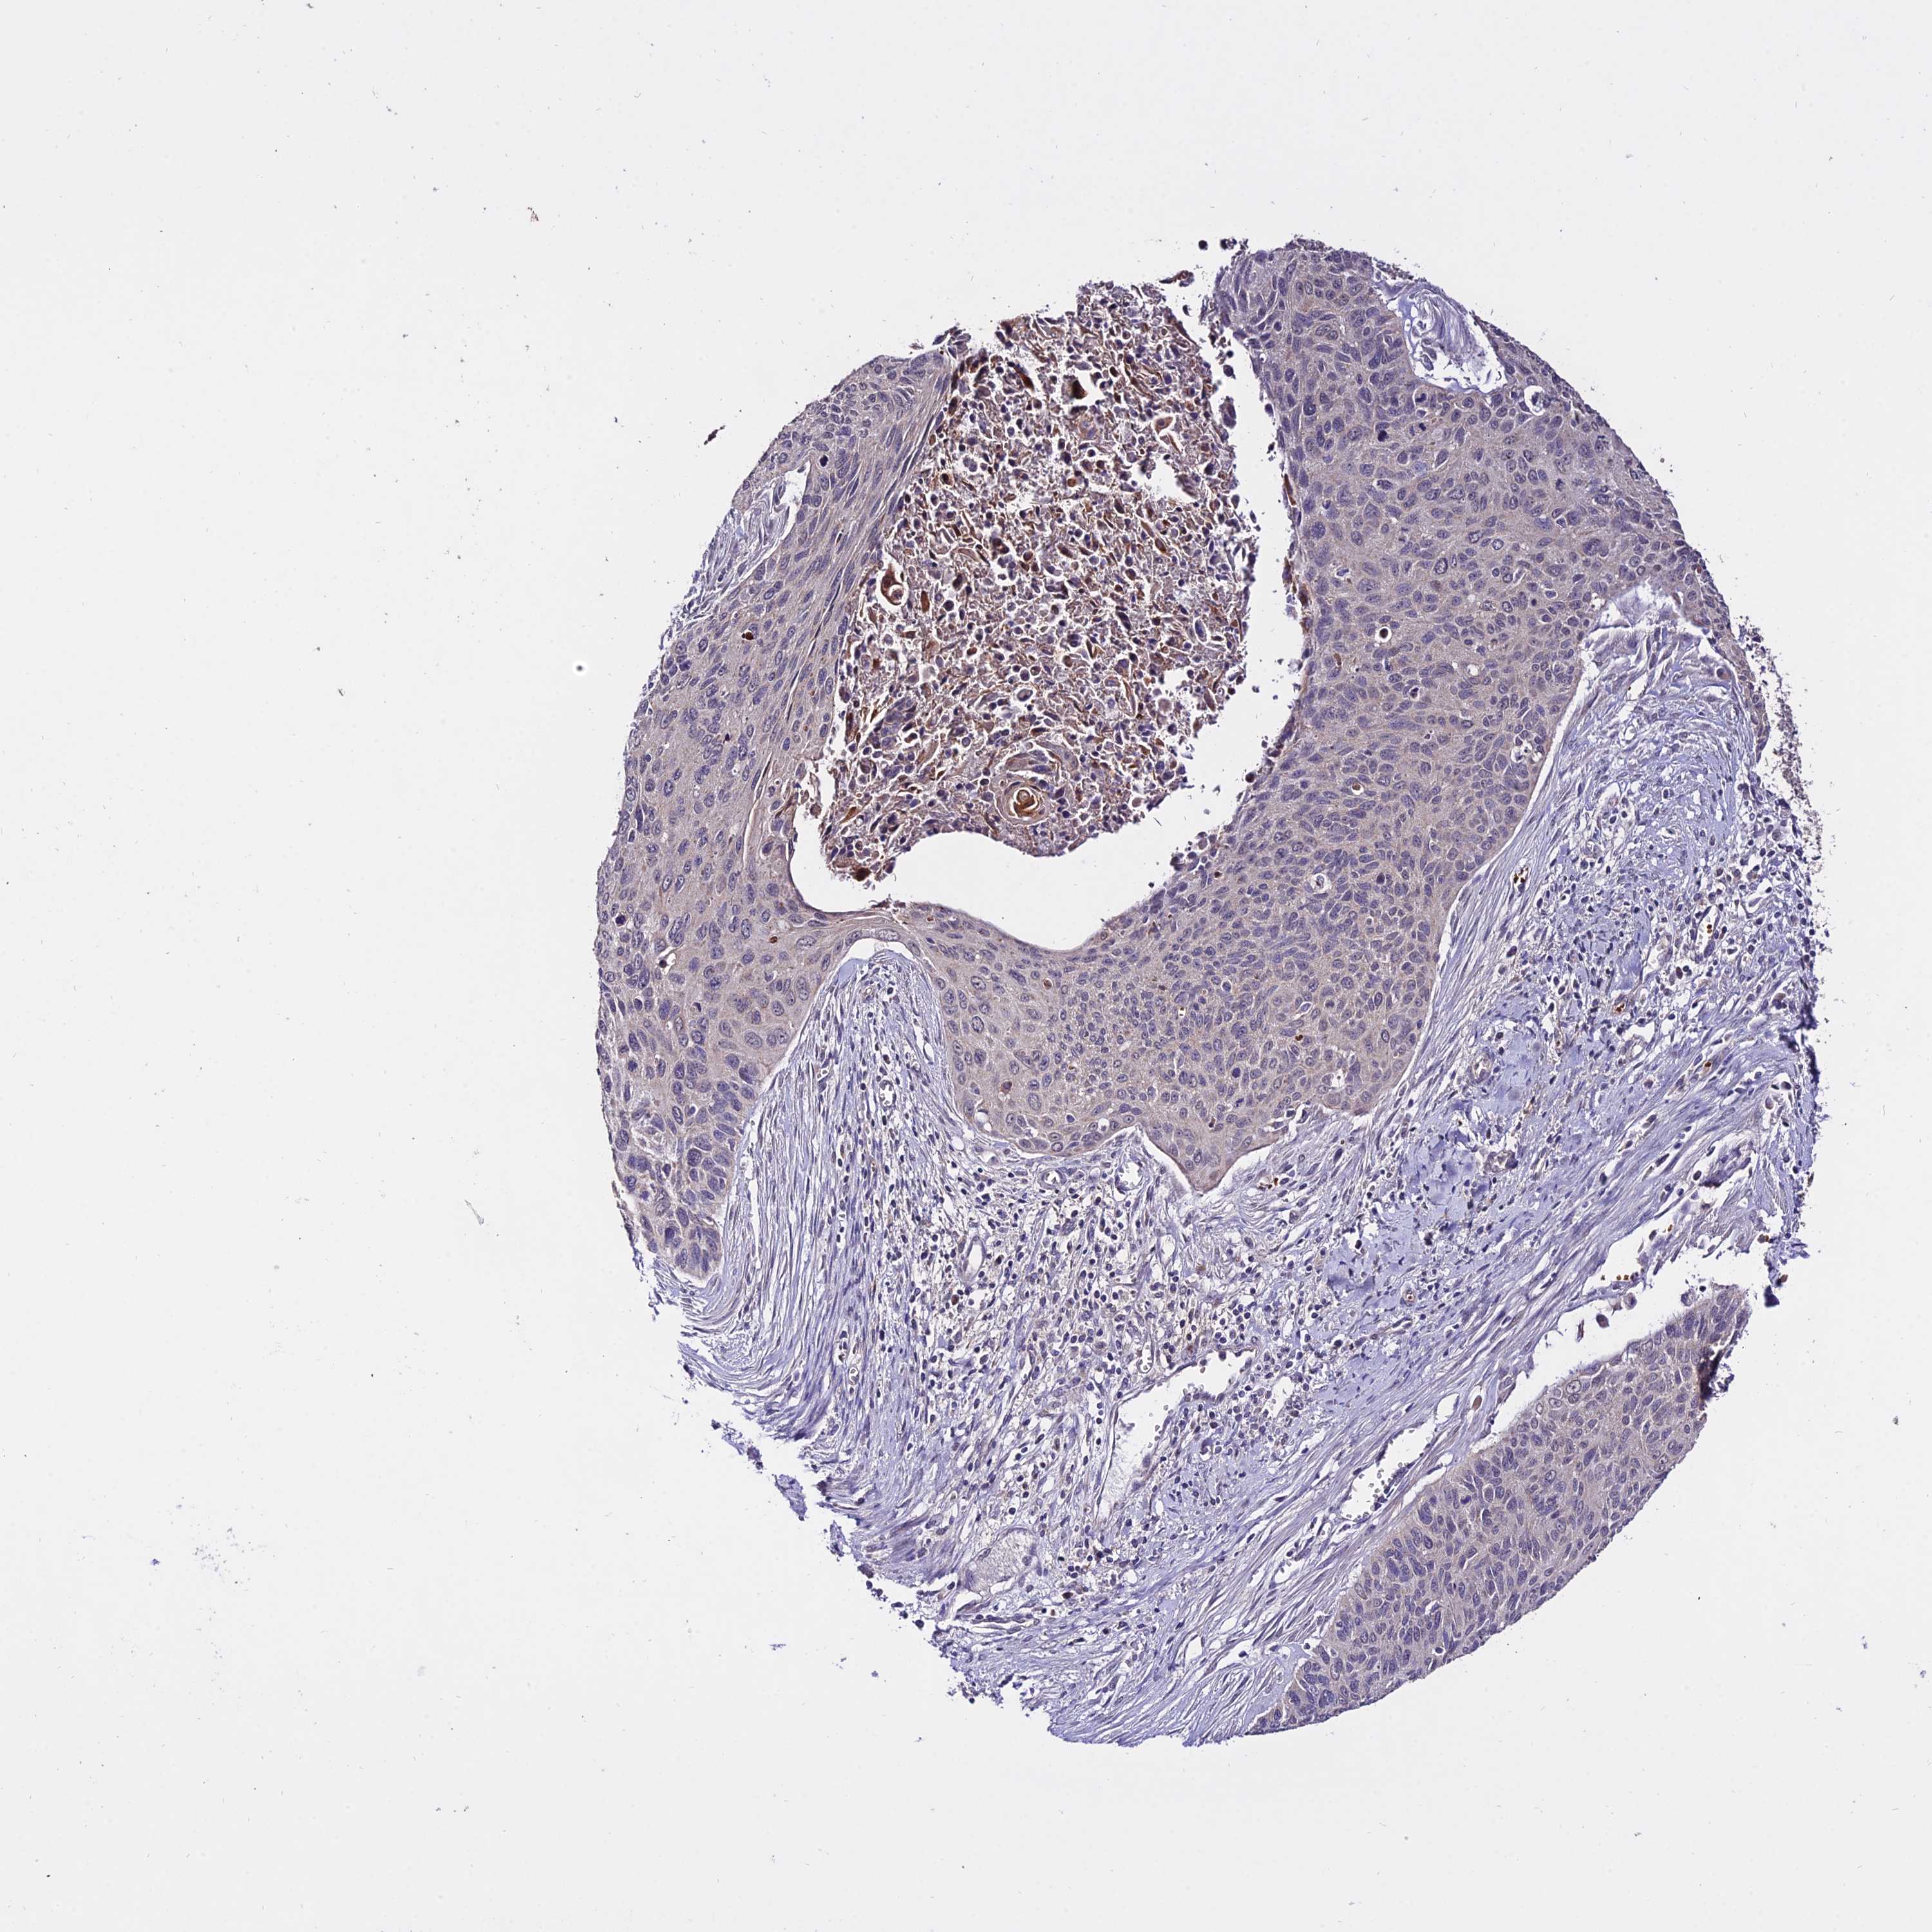

CERVICAL CANCER - Protein expressioni

A mouse-over function shows sample information and annotation data. Click on an image to view it in a full screen mode. Samples can be filtered based on level of antibody staining by selecting one or several of the following categories: high, medium, low and not detected. The assay and annotation is described here.

Note that samples used for immunohistochemistry by the Human Protein Atlas do not correspond to samples in the TCGA dataset.

Antibody stainingi

Antibody staining in the annotated cell types in the current human tissue is reported as not detected, low, medium, or high, based on conventional immunohistochemistry profiling in selected tissues. This score is based on the combination of the staining intensity and fraction of stained cells.

Each image is clickable and will lead to virtual microscopy that enables deeper exploration of all samples and also displays staining intensity scores, fraction scores and subcellular localization as well as patient and tissue information for each sample.

Antibody HPA042994

Staining

High

Medium

Low

Not detected

Intensity

Strong

Moderate

Weak

Negative

Quantity

>75%

75%-25%

<25%

None

Location

Nuclear

Cytoplasmic/membranous

Cytoplasmic/membranous,nuclear

Squamous cell carcinoma, NOS

Adenocarcinoma, NOS